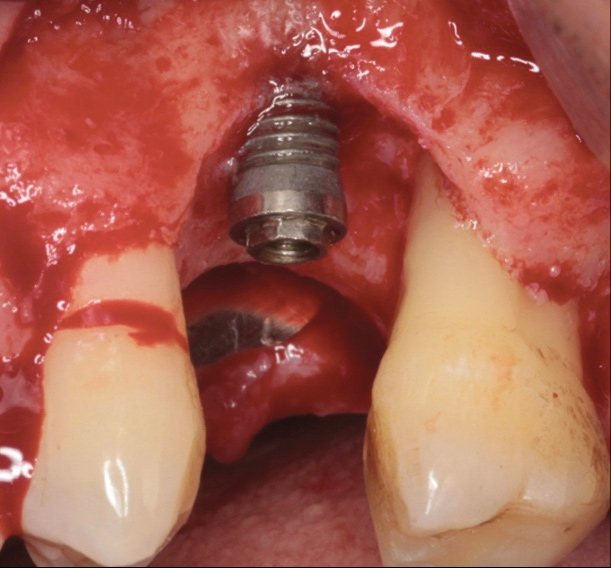

Following a similar paradigm of treating peri-implantitis the same way that periodontitis is regularly successfully treated, based on the mechanical removal of biofilms adhered to implant/abutment surfaces, different protocols of nonsurgical implant debridement using different mechanical, physical, and chemical mechanisms have been evaluated (Figure 12 through Figure 15). In general, the use of different protocols combining treatments aimed to decontaminate the implant surface (eg, mechanical, lasers) and control the infection process (eg, antiseptics, antibiotics) have shown clinical and significant improvements in the commonly used surrogate outcomes (mean reductions in PPD of around 1.2 mm and mean reductions in the scores of BOP of about 50%) but have not resulted in disease resolution18 or a high degree of predictablility.19 There is currently no specific nonsurgical therapy that has shown efficacy in the resolution of peri-implantitis, and the clinical improvements reported in the clinical studies were not sufficient for the arrest of the disease, leaving the standard of care in the treatment of peri-implantitis as surgical in most cases.20

Fig 12. Treatment of peri-implantitis: peri-implant mucosal inflammation associated with plaque and calculus accumulation.

Figure 12

Fig 14. After removing the prosthesis, presence of peri-implant plaque and calculus.

Figure 14

Fig 15. Access flaps to allow mechanical debridement of implant surfaces.

Figure 15